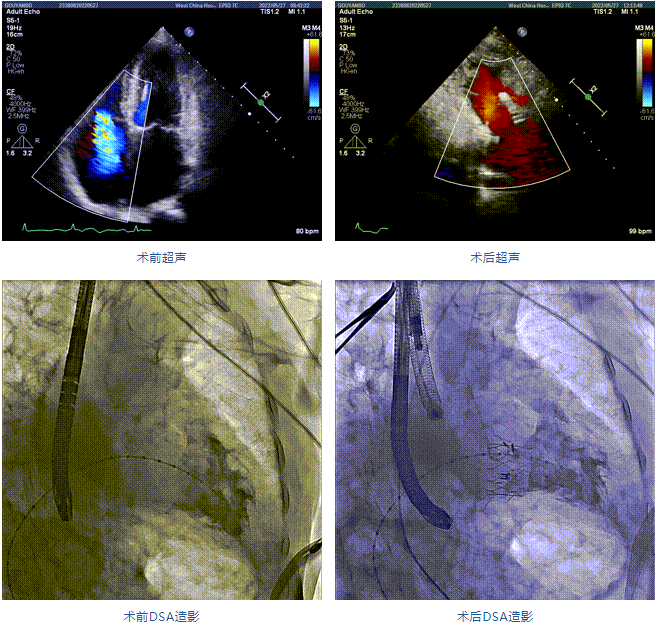

89歲男性。術前超聲報告顯示:雙房增大,左室壁肥厚,主、肺動脈增寬,三尖瓣重度反流。

團隊前期經過多次討論,制定了周密的手術策略和預案。由于患者已是近九旬的超高齡老人,傳統外科開胸手術風險極高,純介入經血管三尖瓣替換能夠明顯減少創傷。術中陳茂及馮沅教授結合體表定位在造影指示下精準穿刺右側頸靜脈并預置兩把血管縫合器。成功建立經皮血管入路后在食道超聲和DSA的引導下順利完成人工瓣膜植入,術后超聲和造影顯示人工三尖瓣同軸性良好,瓣架固定牢靠,無反流和瓣周漏,平均跨瓣壓差降為1mmHg。術畢收緊預置的血管縫合器縫線完成止血,縫合效果滿意,在手術室即刻拔除氣管插管。